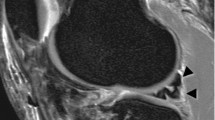

Using the Mimics software, observers were asked to place a circle of 8 pixels in diameter on a sagittal MRI image of their choice, with the other planes and 3D model as a reference, at the center of the patient specific femoral footprint of the ACL. An example is shown in Fig 2. After approximately 1 week the procedure was repeated by the same observers. All observers were blinded to the results of their first session and those of the other observers. As the observers were not trained in Mimics, a medical student trained in Mimics was present at both sessions for practical questions and to ensure smooth logistics.